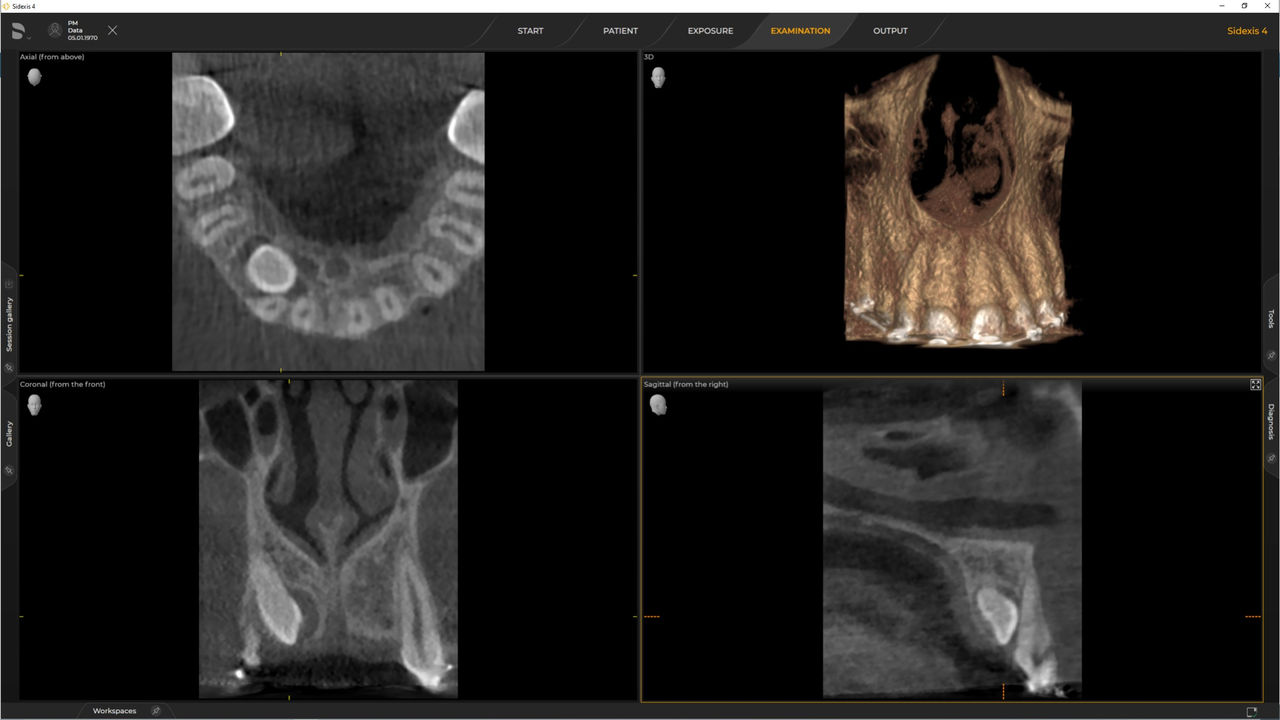

De Ø 5 cm x 5,5 cm a 8 cm x 8 cm u opcional hasta 11 cm x 10 cm

Una amplia gama de tamaños de volumen para satisfacer sus diversas necesidades clínicas y de diagnóstico, desde Ø 5 x 5,5 cm hasta Ø 11 x 10 cm

Con el modo de dosis baja inteligente 3D, obtiene imágenes 3D en el rango de dosis de una imagen radiológica 2D. En el modo HD (hasta 1400), las imágenes individuales se obtienen durante una única rotación y se convierten en un volumen 3D con hasta 80 μm para imágenes de bajo ruido en alta resolución.